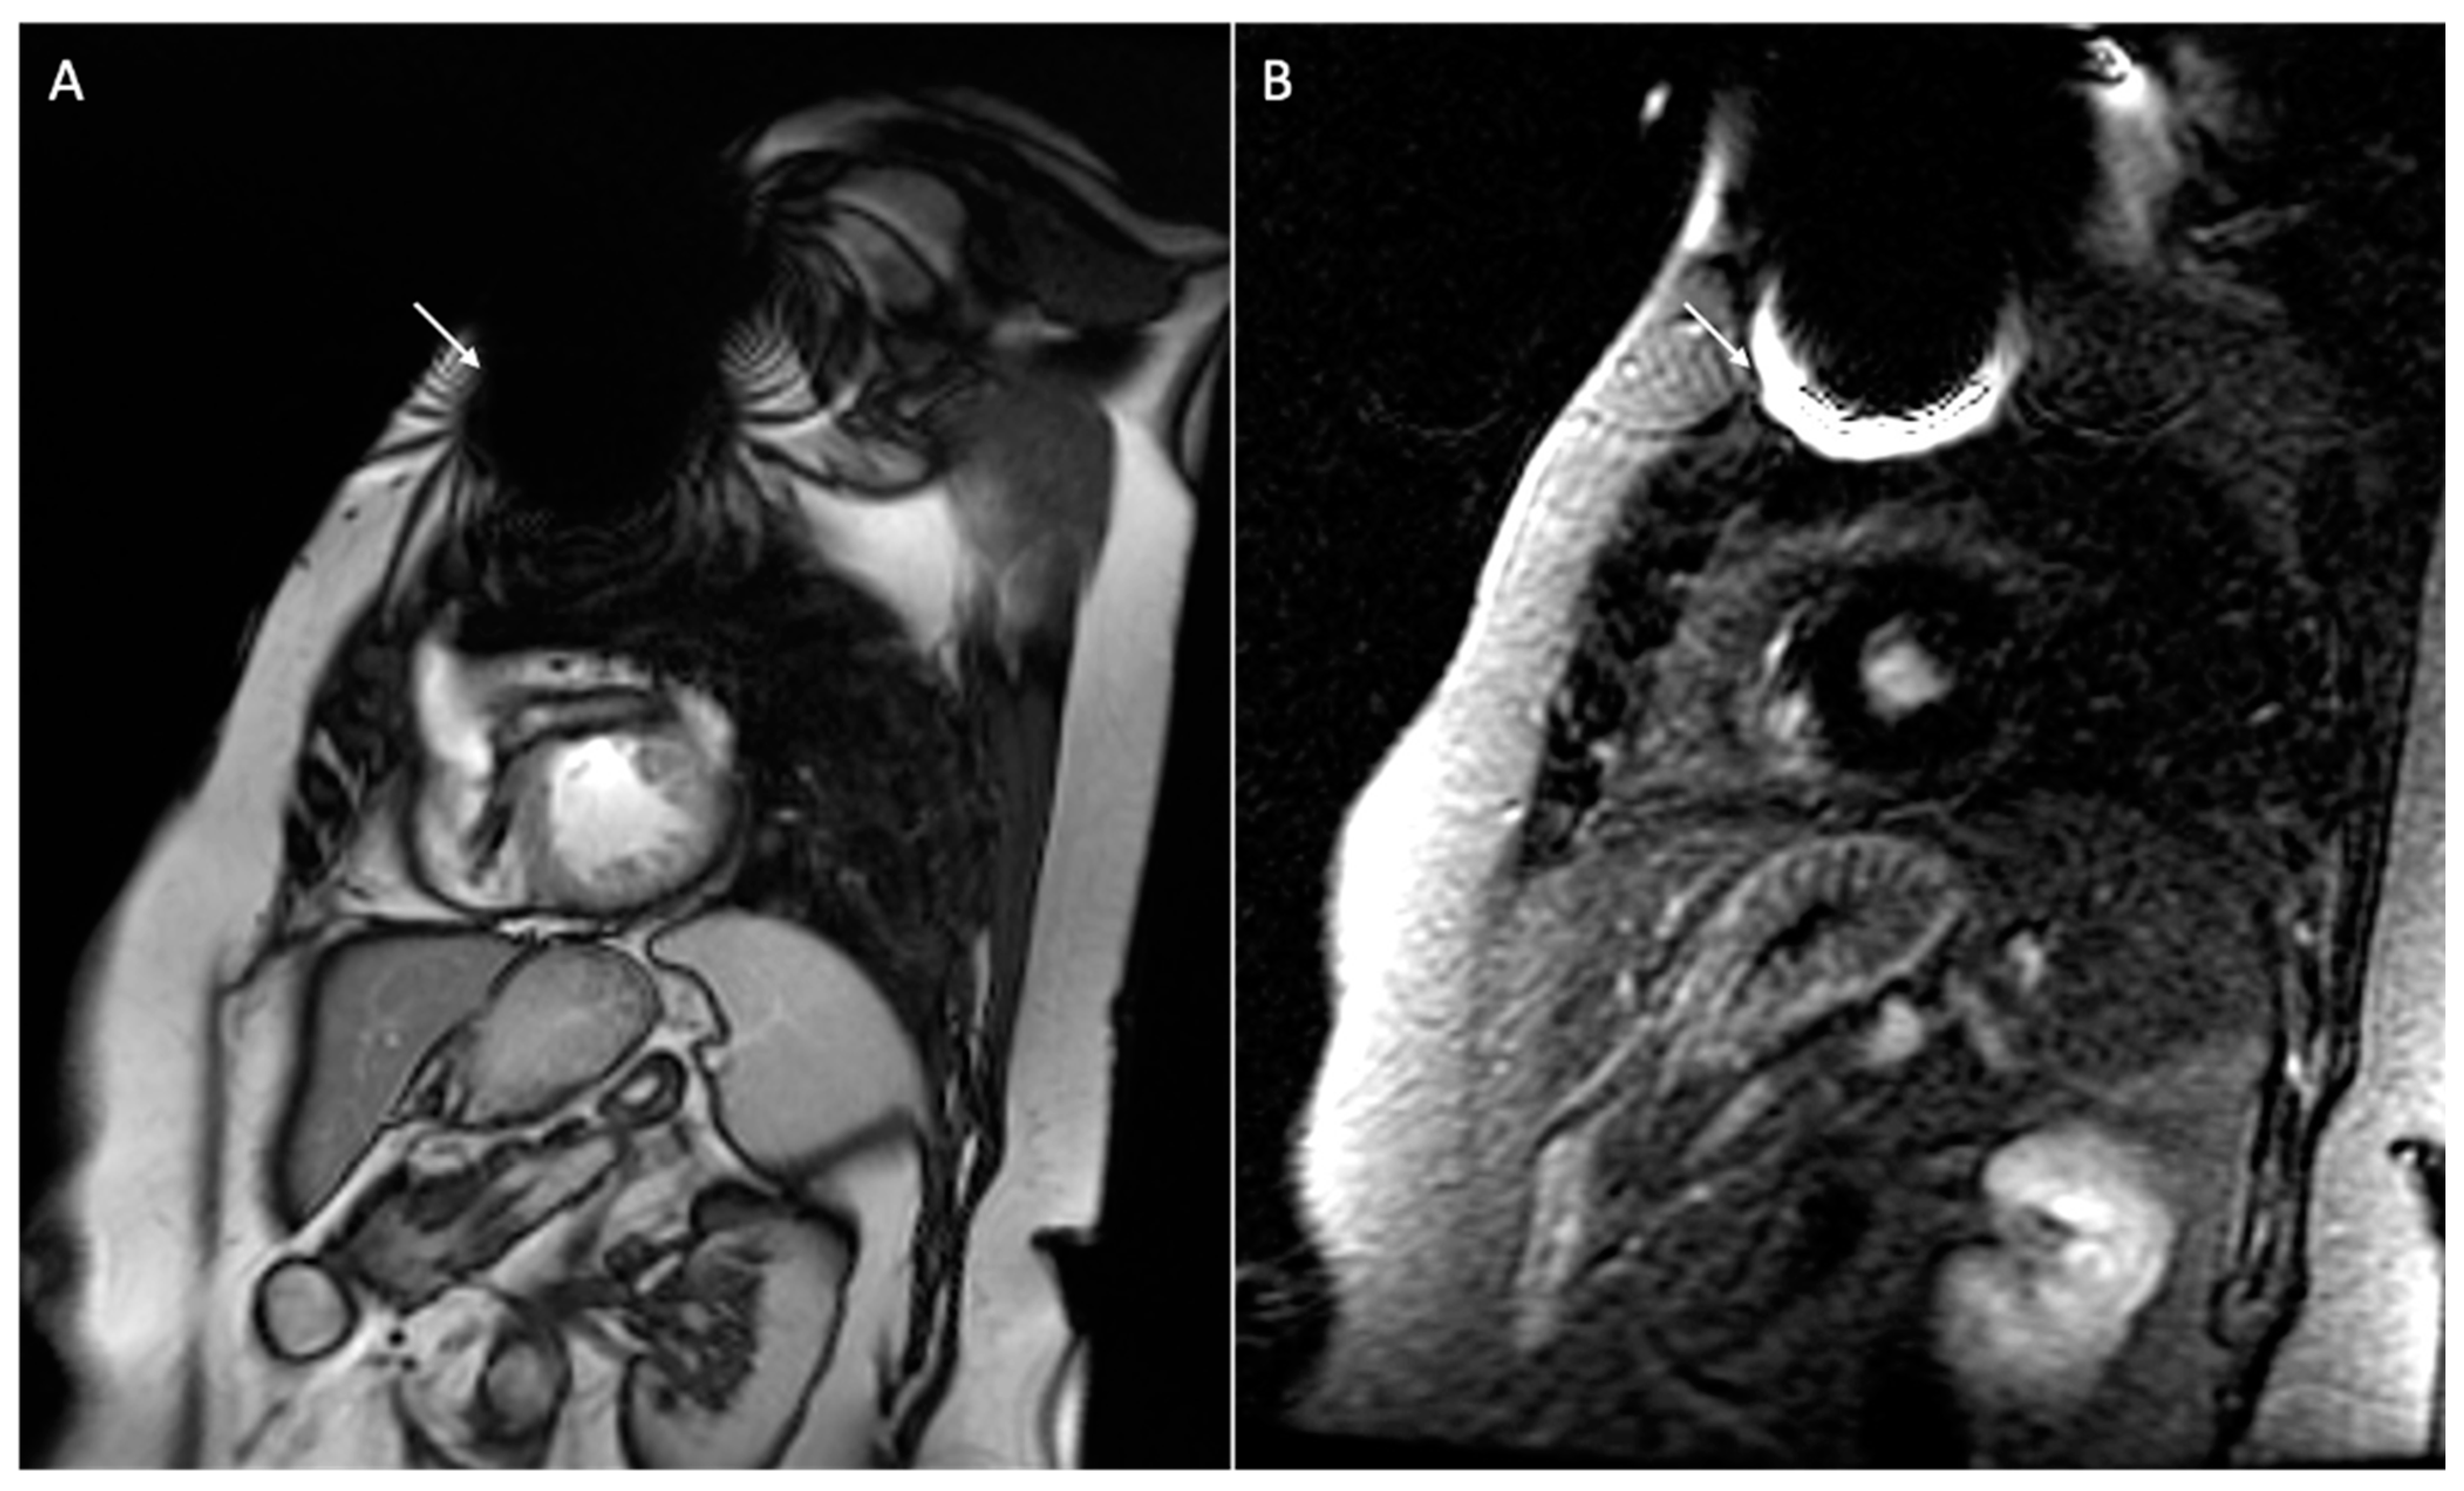

- Vuorinen, A.-M.; Lehmonen, L.; Karvonen, J.; Holmström, M.; Kivistö, S.; Kaasalainen, T. Reducing cardiac implantable electronic device–induced artefacts in cardiac magnetic resonance imaging. Eur. Radiol. 2022, 33, 1229–1242. [Google Scholar] [CrossRef] [PubMed]

| Types of Artifacts | Factors that Influence Artifacts | High Artifact | Low Artifact |

|---|---|---|---|

| Signal loss artifact Hyperintensity artifact | CIED’s dimension | Large device | Small device |

| CIED’s position | Left-sided implantation | Right-sided implantation | |

| Magnetic susceptibility | High ferromagnetic component | Low ferromagnetic components | |

| High static MF | Low static MF | ||

| Distance from the region of interest | Proximity to the heart | Elevate the patient’s arm | |

| MRI sequences used | Cine SSFP | SGE sequences | |

| LGE sequence with a bandwidth of about 1 kHz | LGE sequence with a wide bandwidth |